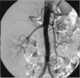

Livedo reticularis is a common skin finding consisting of a mottled reticulated vascular pattern that appears as a lace-like purplish discoloration of the skin. The discoloration is caused by reduction in blood flow through the arterioles that supply the cutaneous capillaries, resulting in deoxygenated blood showing as blue discoloration. [Source: Wikipedia ]